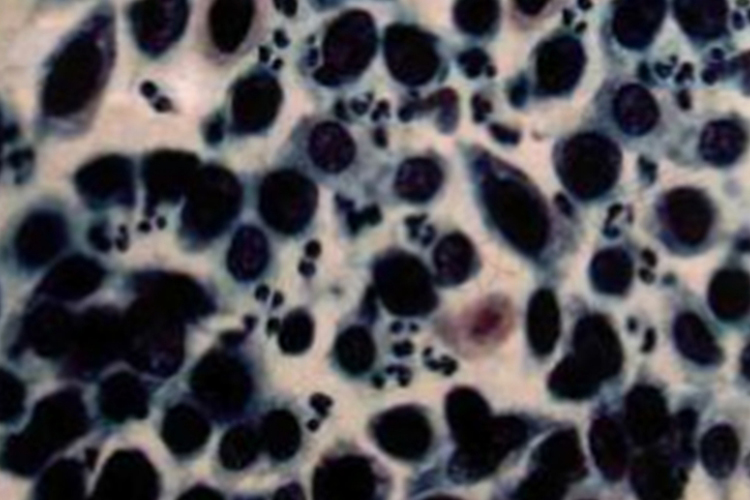

小细胞未分化癌:癌细胞排列紧密,多成束出现;胞体小,胞质更少,似裸核,核质比增大显著;核呈不规则的圆形、瓜子形、燕麦形,核染色质粗、不均匀。